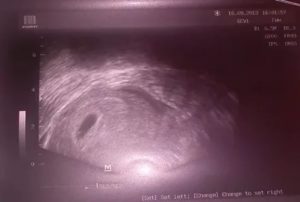

Диагностика внематочной беременности

Одним из показаний для проведения ультразвукового исследования на 6 неделе беременности является подозрение на внематочное расположение плодного яйца. Подобный диагноз зачастую устанавливается именно в этом сроке. Плодное яйцо может обнаруживаться в одной из маточных труб, в цервикальном канале, в брюшной полости.

В случае если возникает вопрос о сроке беременности, можно определить уровень хорионического гонадотропина. При его значении 1500 ед/мл и больше плодное яйцо должно быть обнаружено в матке. Если этого не происходит, то говорят о внематочной беременности.

При выполнении УЗИ следует учитывать, что при эктопическом расположении эмбриона в центре матки может визуализироваться ложное плодное яйцо. Оно представляет собой анэхогенное образование округлой или неправильной формы диаметром до 10 мм.

Образуется оно из децидуально изменённого эндометрия.

При выявлении жидкости в малом тазу необходимо исключить нарушенную маточную беременность с развитием внутрибрюшного кровотечения.